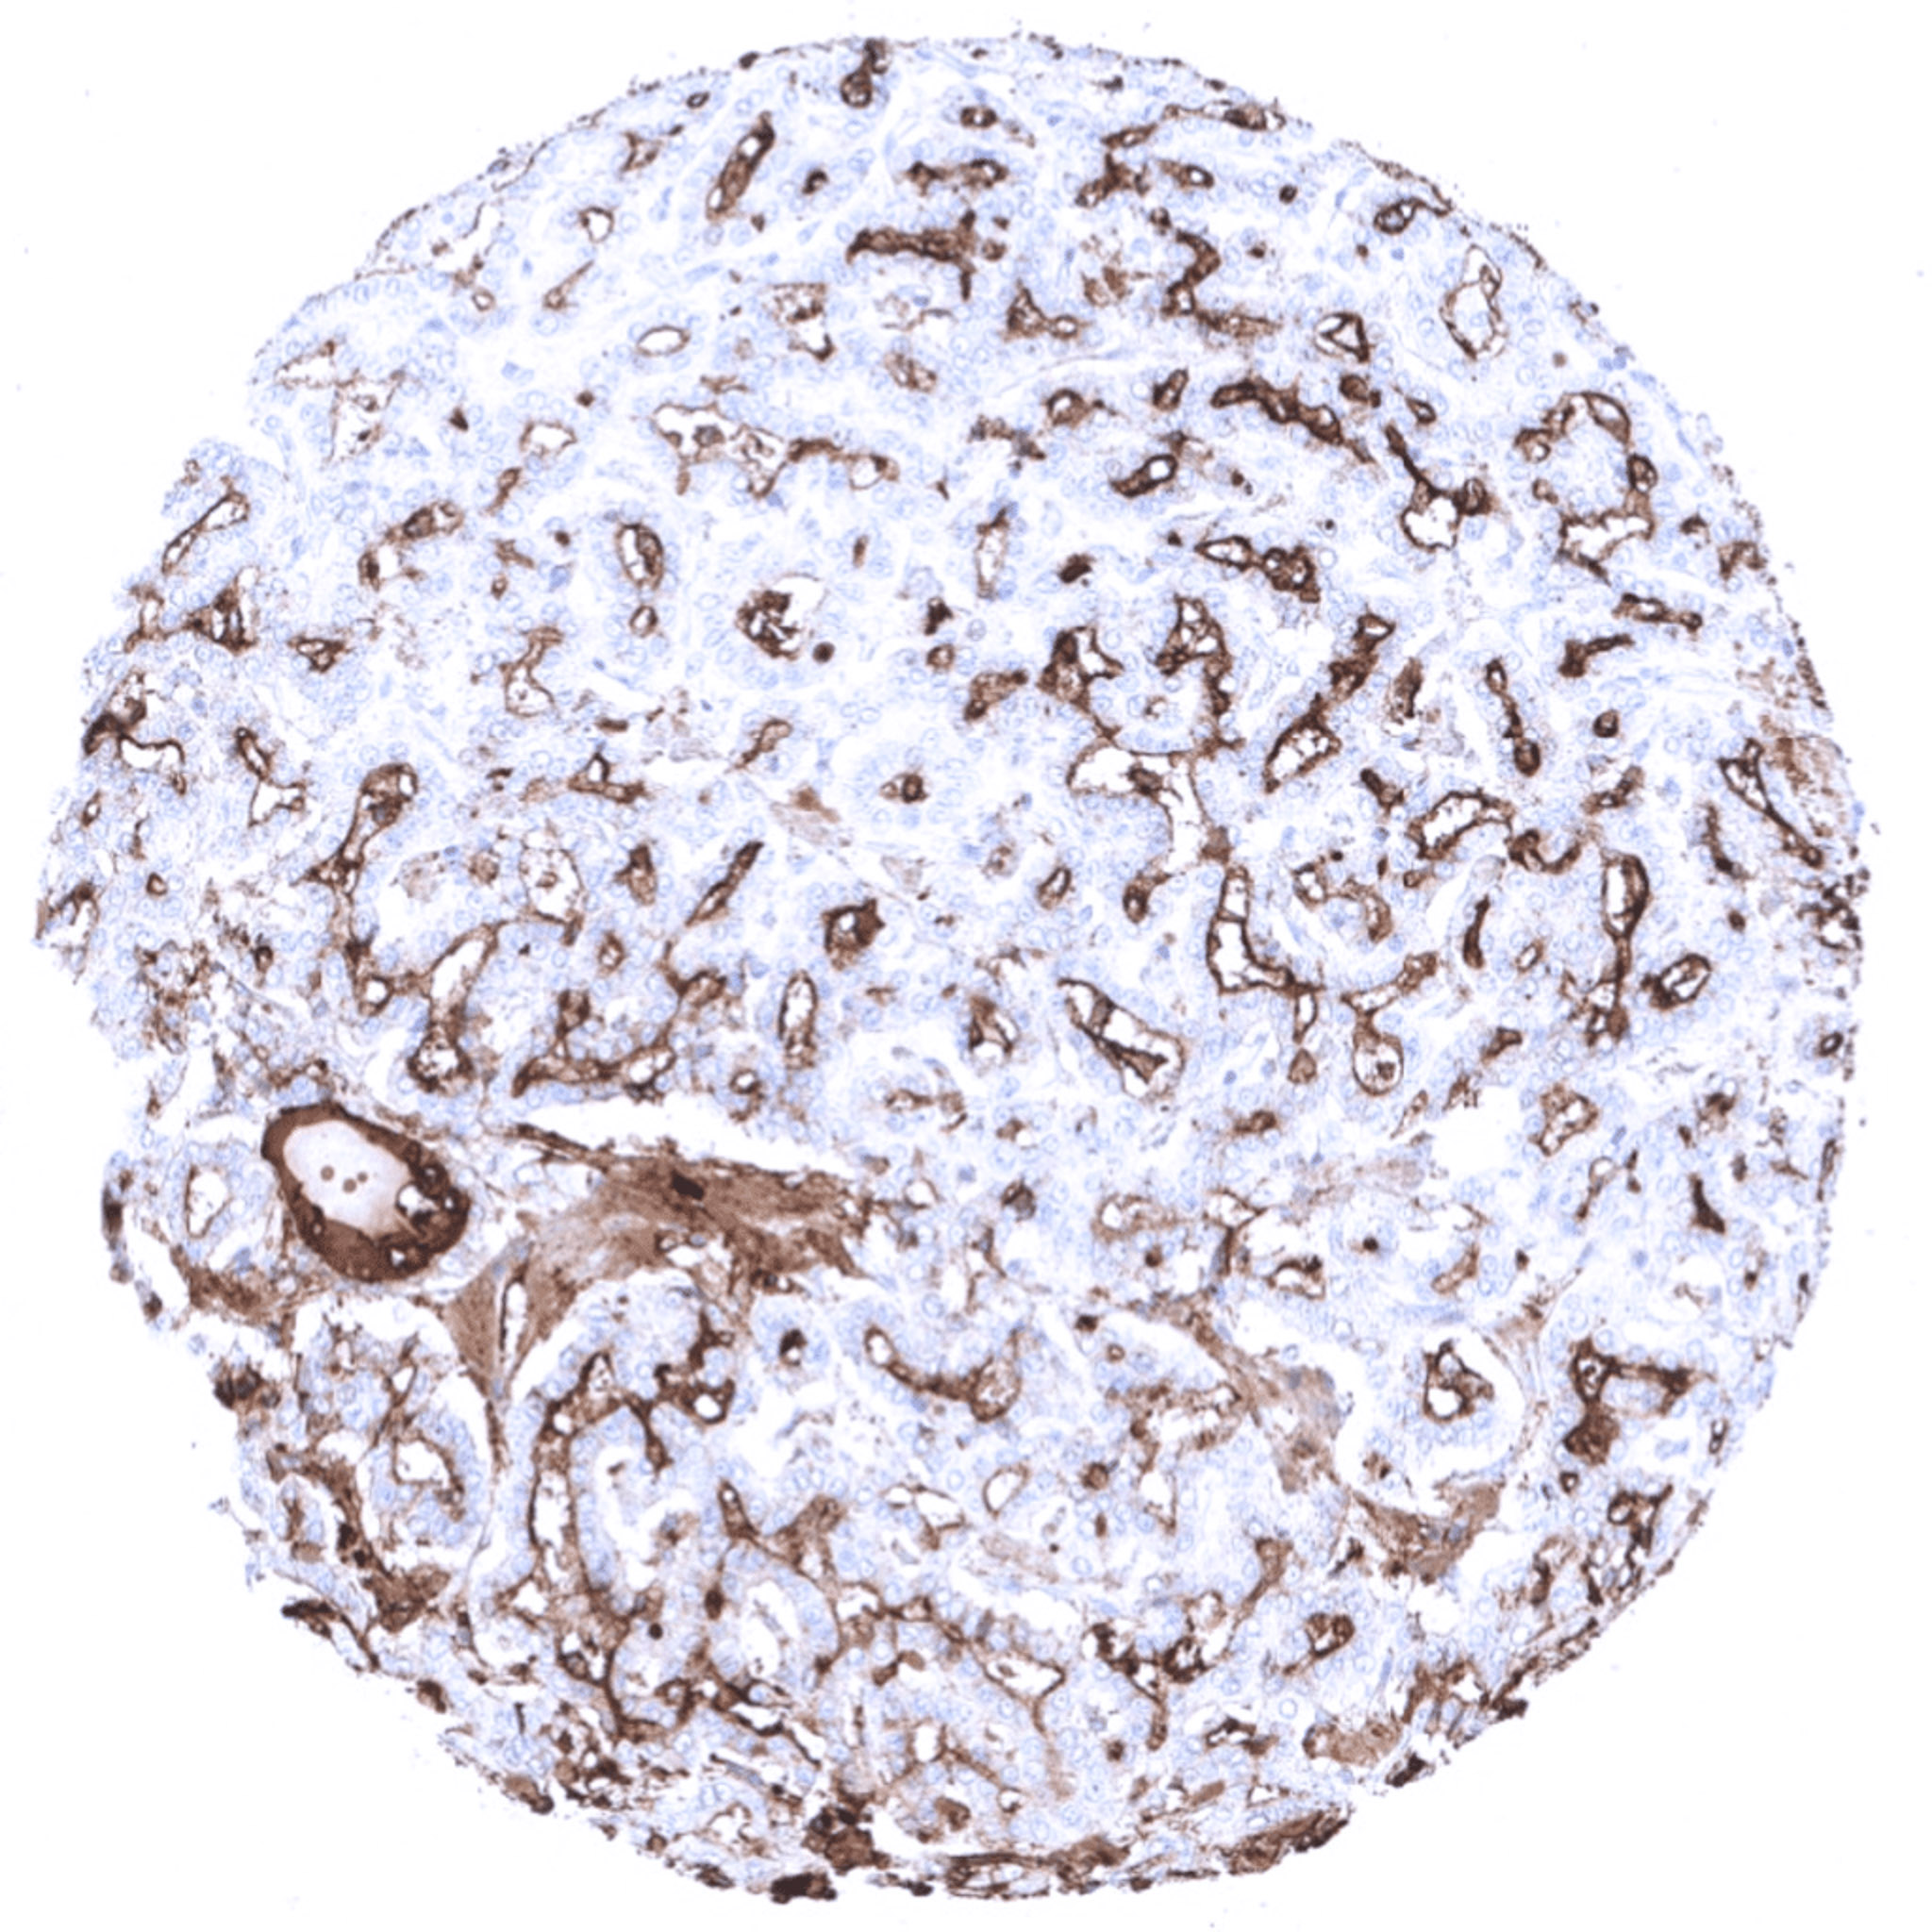

Follicular thyroid cancer with moderate thyroglobulin immunostaining.